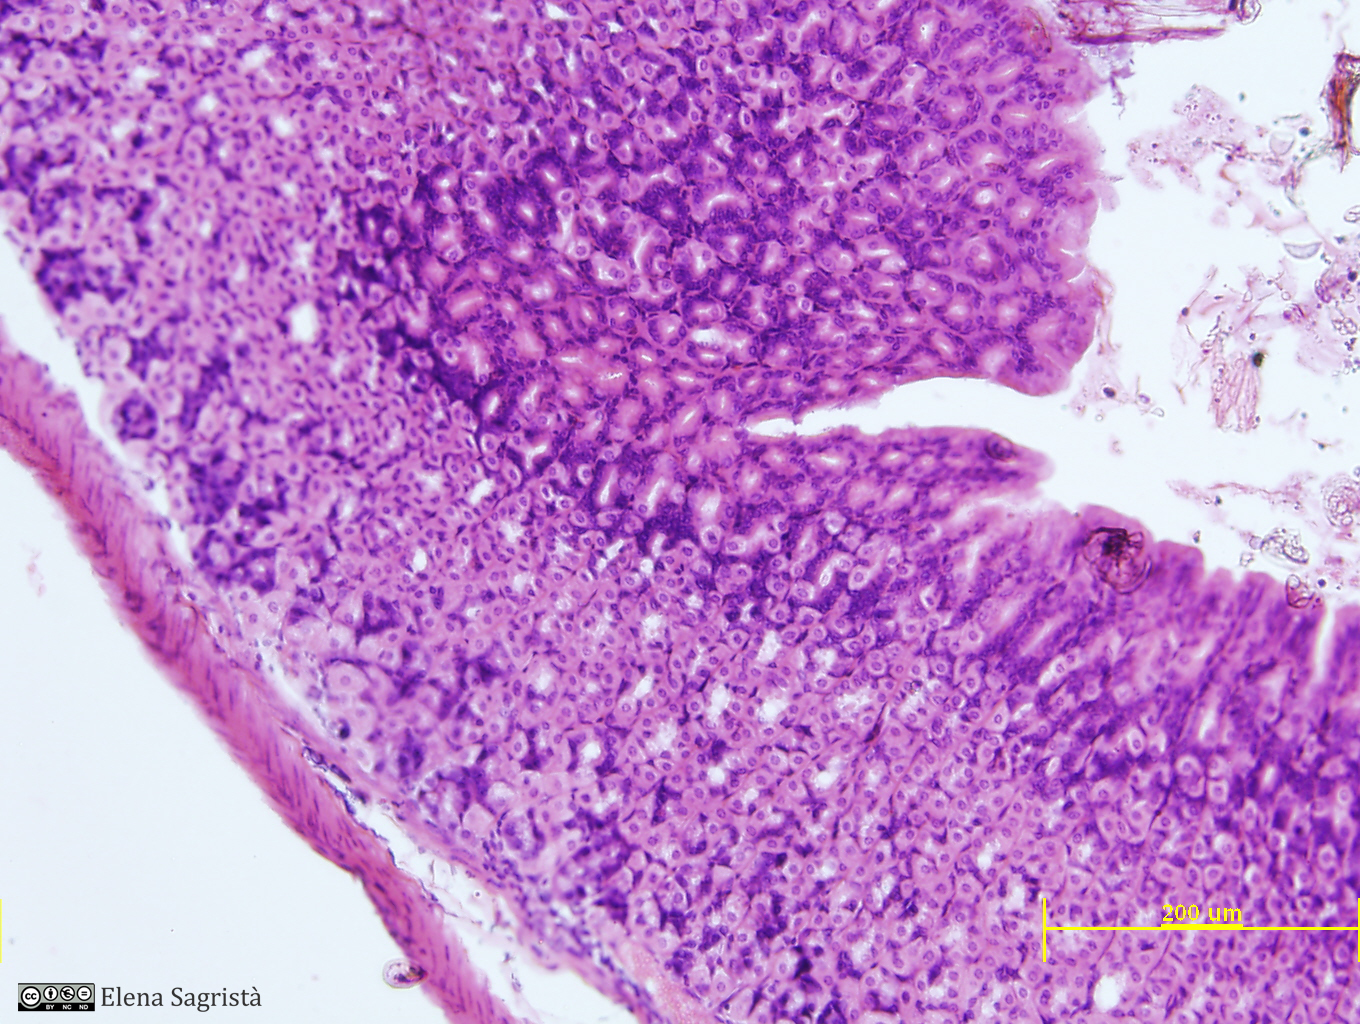

Histologia imatges: 16 Estòmac

Imatges de preparacions histològiques d'Estómac. Microscopia òptica.